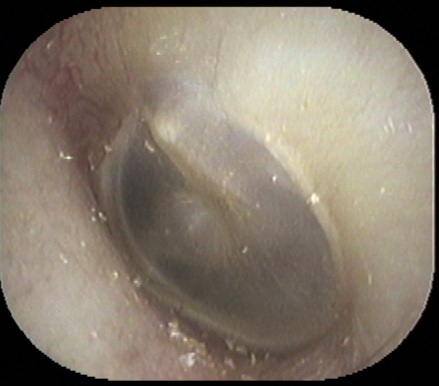

まずは正常な耳所見です↓

そして今回の患者さんの耳です↓

外耳道(耳の入り口から鼓膜までの皮膚部分)が、すごく腫れていました。

病名は急性外耳炎です。

毎日 綿棒と耳かきで掃除していたとのこと。ここまで腫れると聞こえが悪くなります。